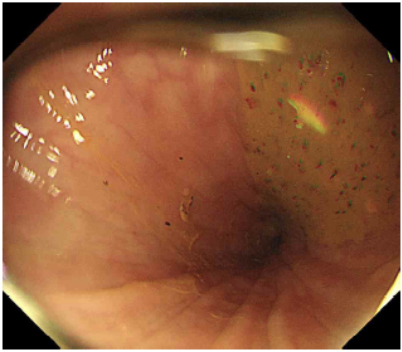

Sigmoidoscopy: Endoscopic eveidence of obstruction

• 이어 촬영한 AXR상 "coffee-bean sign"이 명확히 관찰되는데, 이는 구불창자꼬임을 시사하는 소견이다. 추가적으로 sigmoidoscopy상 intestinal obstruction 소견 또한 관찰할 수 있다.

• 대장거짓폐쇄: 대장거짓폐색는 장내 병변이 없는 장폐색 증상이 나타나는 경우 의심할 수 있다. 현재 환자는 AXR 및 sigmoidoscopy상 구불창자의 꼬임 및 폐쇄가 관찰되므로 구불창자꼬임으로 진단하는 것이 적절하다.